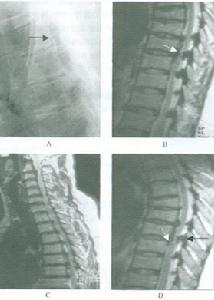

頸椎黃韌帶骨化症X線平片黃韌帶骨化陰影常與椎體影像重疊而難以辨別。在側位片上,可見椎板腹側或椎板之間有密度增高的骨化塊陰影,下緣起於下一椎板上緣,上緣終止於該椎板中1/2處,其形狀常為三角形,如骨化灶較小或辨認有困難的,可攝斷層片以進一步明確診斷。

脊髓造影表現為同骨化水平相一致的完全性梗阻或不完全性硬阻,在X線片上常可見不完全梗阻的壓迫來源來自於硬膜囊的後方。

CT掃描可清晰地顯示位於頸椎椎板腹側的團塊狀骨化灶,並向椎管內突出,壓迫頸脊髓,其CT值與骨相同,如作CT脊髓造影檢查,可見頸脊髓硬膜囊受壓移位情況,進一步判定其受壓程度。

MRI檢查在MRI的T1及T2加權矢狀面圖像上,增厚、骨化的黃韌帶常低信號影凸向椎管,造成頸椎背側硬膜囊壓迫。頸椎黃韌帶退變增厚時,在T1、T2加權時也呈等信號低信號突向椎管,但兩者在形態上常不盡相同,黃韌帶退變時常為多節段、半圓形陰影,而骨化灶則為單節段三角形影,而且壓迫程度更為嚴重。

有學者指出,黃韌帶骨化灶與其他骨組織一樣含有骨髓及脂肪組織,在T1加權上也可呈高信號影,並有人對在MRI圖像上呈不同信號程度的黃韌帶骨化組織進行相應的病理及免疫組化研究,發現MIR上是等信號強度區域為肥厚的韌帶中增生的小血管,標誌著骨化進展期的開始。

儘管在橫斷面圖像上,MRI顯示頸椎黃韌帶骨化不及CT掃描清晰,但其可直接進行矢狀面成像,除顯示骨化對脊髓壓迫程度之外,還可反映出脊髓受壓後的信號變化情況,判斷疾病預後。